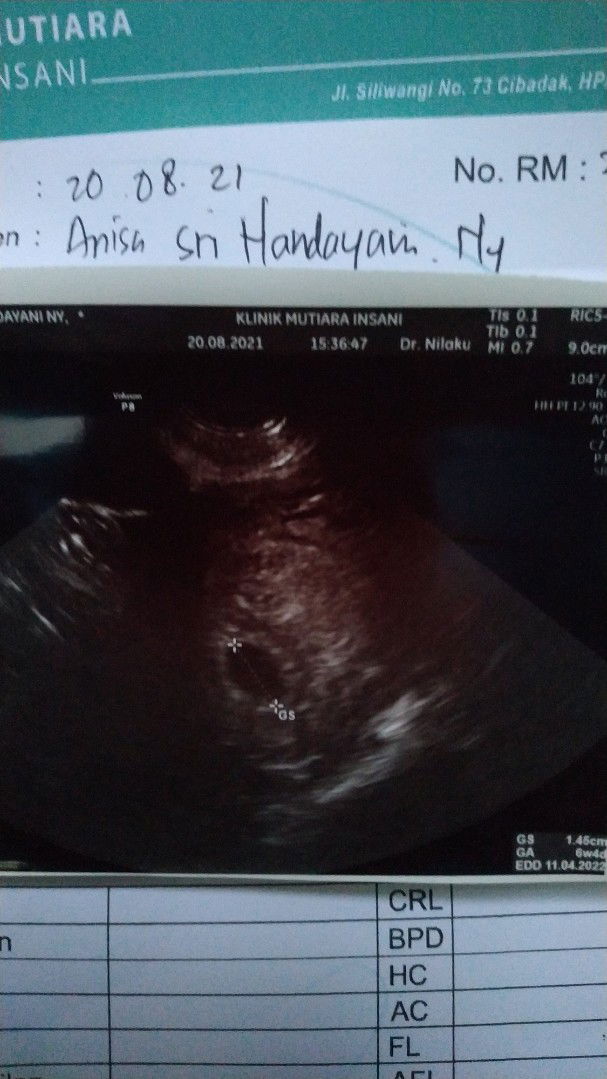

Bunda aku mau tanya, klo arti letak janin di buku kia itu sebelah kanan atau kiri?

bisa kiri bisa kanan bun. perhatiin aja gerakannya lebih aktif di sisi mana. Contoh kalau gerakan berada di bagian kiri berarti punggung janin berada d bagian kanan, bgtu jga sebaliknya